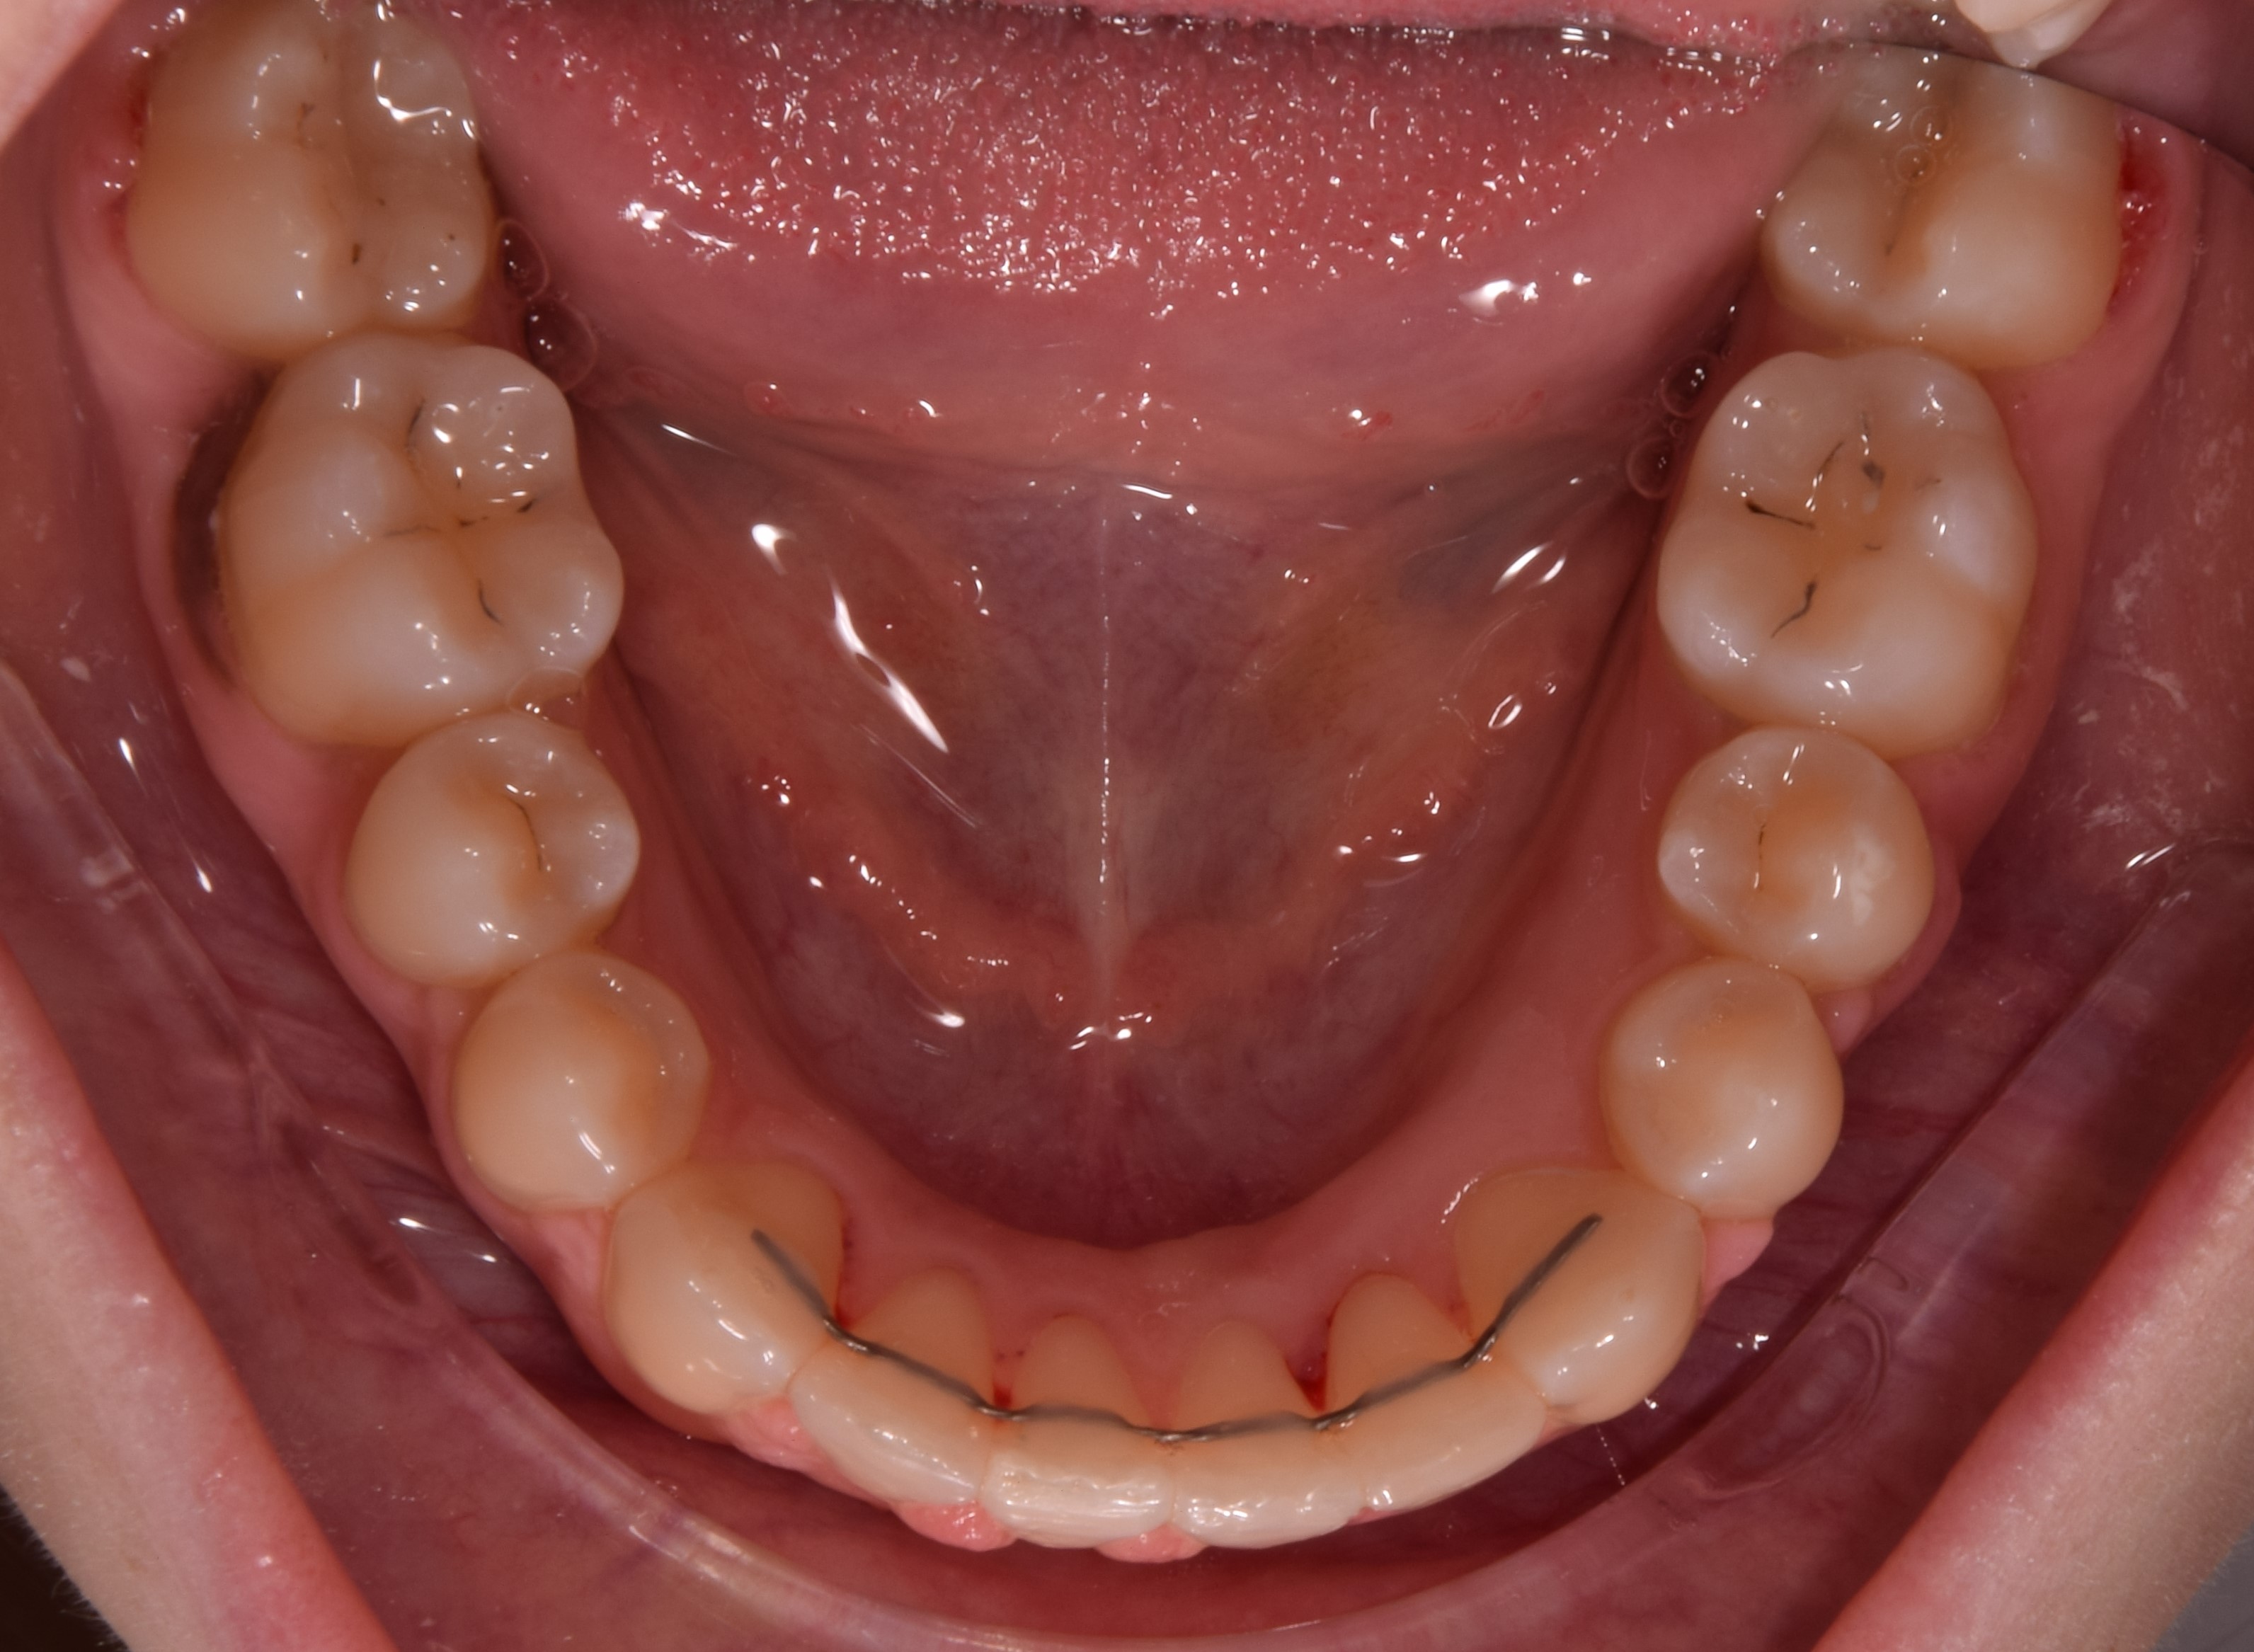

Fix retainer és MRI – kisebb kockázat, de nem elhanyagolható

A fix retainer, amelyet a fogszabályozás után rögzítenek a fogak belső oldalára, általában vékony drótból áll. Bár mérete kisebb, mégis befolyásolhatja az MRI felvételek minőségét, ha a vizsgálat a fej, az állkapocs vagy a nyaki területre koncentrál.

Fontos azonban megjegyezni, hogy a fix retainer által okozott torzulás jellemzően kisebb mértékű, mint a teljes rögzített fogszabályozó készüléké, de bizonyos esetekben ez is problémás lehet.